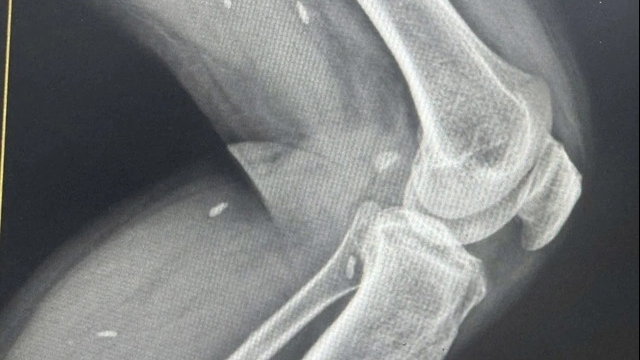

| Trẻ từ 5 đến dưới 12 tuổi được tiêm vắc xin COVID-19 tại Phòng khám đa Yên Hòa, TTYT Cầu Giấy |